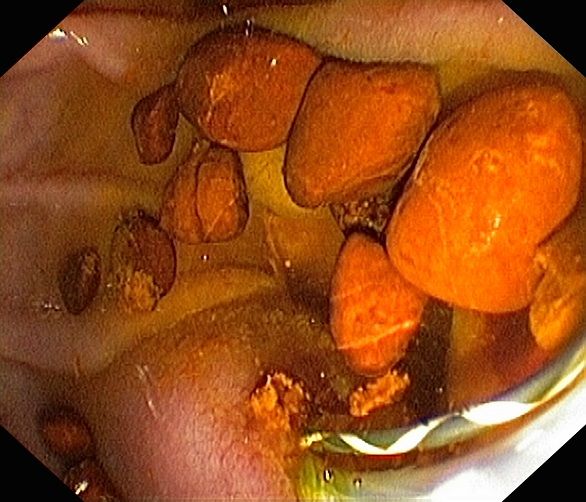

- Spaltung der Papille (Organ, in dem Gallen- und Bauchspeicheldrüsengang in den Dünndarm münden) zur Verbesserung des Galleabflusses

- Entfernung von Gallensteinen, mechanische Steinzertrümmerung (Lithotrypsie)

Die Untersuchung wird in Bauchlage durchgeführt. Aus Sicht des Patienten ähnelt sie der Magenspiegelung, allerdings wird das Endoskop tiefer in den Zwölffingerdarm platziert, so dass die Gallengangsmündung (Papille) zu sehen ist. In diese wird Kontrastmittel eingespritzt, und so die Gallengänge unter Röntgendurchleuchtung sichtbar gemacht. Ist beispielsweise ein Abflusshindernis in den Gängen durch Gallensteine vorhanden, kann dies nun endoskopisch mit verschiedenen Methoden beseitigt werden.